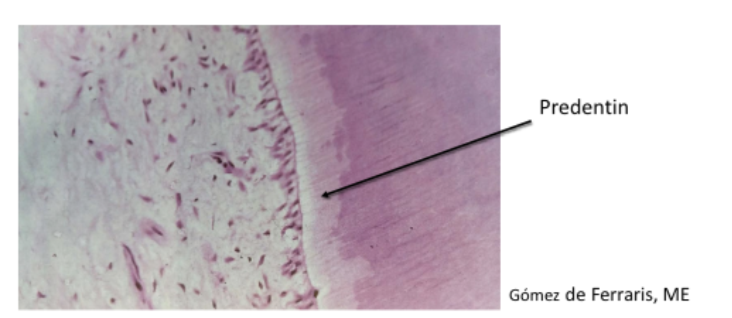

Predentin

• It is the unmineralized zone of dentin immediately next to the pulp.

• 30 μm thick

• Odontoblasts initially form predentin, which undergoes mineralization and becomes

dentin.

Once organic matrix is secreted, the matrix is mineralized, but only up to a

point where there is a small layer of unmineralized organic matrix between

the odontoblast cell body.

This unmineralized matrix layer is called predentin. It is always present throughout dentinogenesis between the odontoblast cell body and the mineralized portion of dentin.